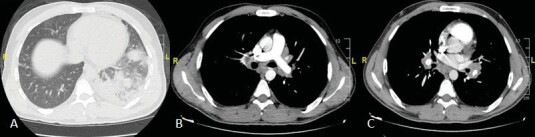

Tuberculosis (TB) is an airborne infectious disease caused by Mycobacterium tuberculosis (MTB). Although it typically affects the lungs (pulmonary TB), one-fifth of TB cases present as extrapulmonary TB. The diagnosis of extrapulmonary TB is often overlooked due to its atypical clinical and radiological manifestations. Differentiating TB from neoplastic conditions poses significant challenges. A 33-year-old female patient was admitted to the emergency clinic with shortness of breath, cough, and abdominal pain. Postero-anterior chest X-ray revealed massive pleural effusion leading to mediastinal shift. With a preliminary diagnosis of malignant pleural effusion, a pleural catheter was inserted, and the patient was referred for a positron emission tomography (PET/CT) to assess the primary site and the optimal location for a biopsy. The PET/CT revealed asymmetric soft tissue thickening on the left side of the nasopharynx, and increased fluorodeoxyglucose (FDG) uptake in the left cervical lymph nodes raised suspicion regarding primary nasopharyngeal cancer. Additionally, there was an increased FDG uptake observed in the mass lesion located in the right upper lobe, mediastinal lymph nodes, pleural surfaces in the left hemithorax, perihepatic areas, and peritoneum, indicating diffuse metastatic disease. Tuberculosis diagnosis was confirmed through biopsies demonstrating granulomatous inflammation in the lung and nasopharynx, along with culturing MTB from pleural effusion. Positron emission tomography played a crucial role in identifying sites of TB involvement. Despite its rarity, healthcare professionals should consider nasopharyngeal TB as a potential diagnosis when evaluating nasopharyngeal masses.